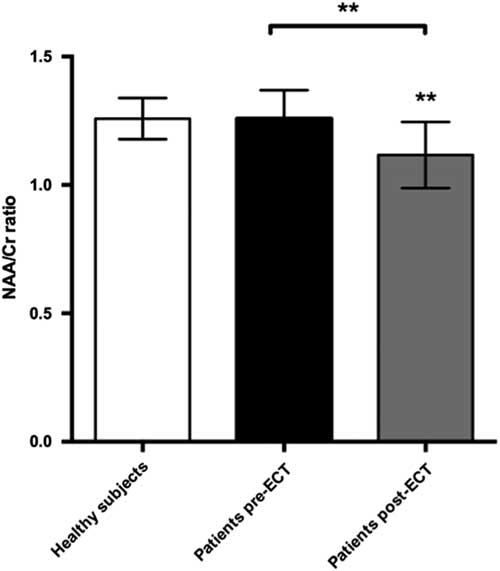

Other metabolites of interest

We found a significant decrease in the NAA/Cr ratios in the PFC during ECT, t(22)=3.89, p=0.0038. Cohen’s d was 1.18, representing a large effect size. This was still significant after a Bonferroni correction for the six tests made on prefrontal changes with ECT (giving a corrected p-value of 0.08). There was no significant difference when comparing baseline NAA/Cr levels between patients and healthy subjects. However, post-ECT NAA/Cr ratios were significantly lower in patients compared with healthy subjects, t(21)=2.9, p=0.007 (Fig. 5). Cohen’s d was 1.36. Finally, we found a significant correlation between numbers of ECT sessions and NAA/Cr change (p=0.035), with NAA/Cr ratios decreasing as the number of ECT sessions increased.

Fig. 5 Plot of NAA:Cr ratios in prefrontal cortex showing mean ± SD. ECT, electroconvulsive therapy; NAA, N-acetylaspartate.

To investigate whether the observed difference in NAA/Cr was caused by differences in GM content within the voxel we compared the fraction of GM from the segmented T1 image between healthy subjects (GM 0.56±0.05) and patients at baseline (GM 0.53±0.06), but found no significant difference (p=0.37). Also, post-ECT GM content (GM 0.55±0.06) did not differ significantly from baseline (p=0.35). Due to technical issues segmentation was only performed in nine patients and 11 healthy subjects.